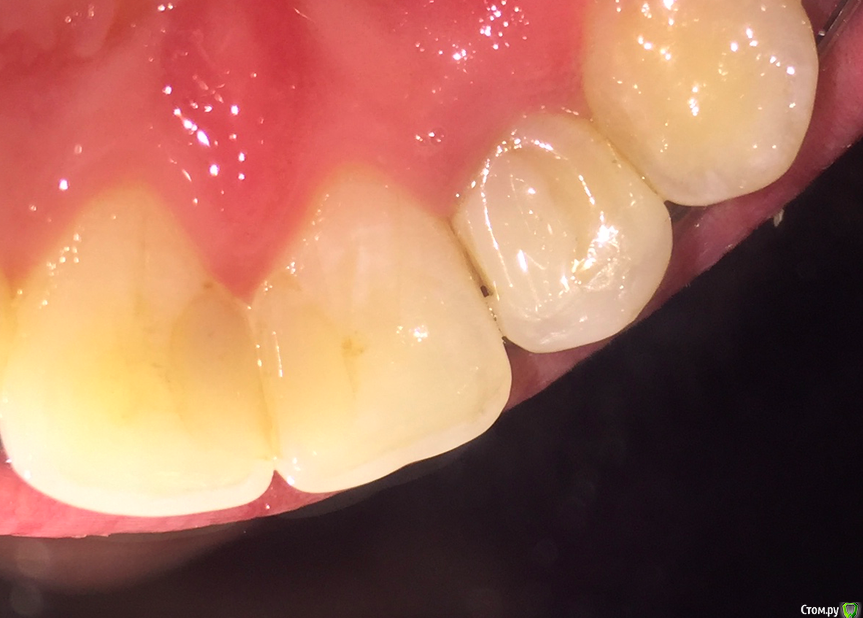

Zubik_Zubik Опубликовано 18 февраля, 2019 Поделиться Опубликовано 18 февраля, 2019 (изменено) Добрый день!22 депульпирован более 10 лет назад. пломба, затем реставрация, брекеты, сейчас повторная реставрация чтобы приклеить ретейнер.Скололся из за нависающего края на медиальной стороне.1. Что разумнее сделать?- предлагают устранить скол пломбой- снять так, ортопедия 4 зуба например. 2. можно ли будет поставить коронку если пломба у десны при условии что хочу все красиво?)Спасибо! Изменено 18 февраля, 2019 пользователем Zubik_Zubik Ссылка на комментарий

Zubik_Zubik Опубликовано 1 марта, 2019 Автор Поделиться Опубликовано 1 марта, 2019 (изменено) Как смог нарезал в кт. 1.Ортопед сказал что с небной подрезать нужно чутка.2.Насколько разумен такой вариант пока установлены брекеты. Спелить пломбу переклеить брекет с целью экструзии зуба, потом снова пломба и ретейнер. После небольшого отдыха нормальная коронка +3 винира 21, 11, 12. Спасибо Изменено 1 марта, 2019 пользователем Zubik_Zubik Ссылка на комментарий